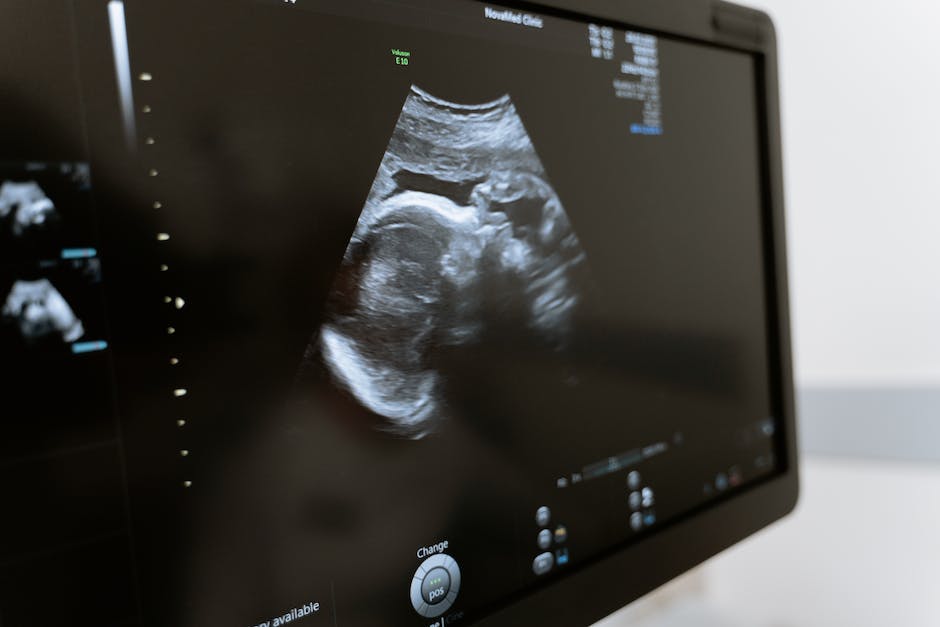

수원산부인과병원은 최신 시술과 기술을 적극적으로 도입하여 정확하고 신속한 진단과 효과적인 치료를 제공합니다. 초음파, 조직 검사, 유방 초음파, 유방 조직 검사 등 다양한 검사와 검진을 통해 정확한 진단을 내릴 수 있습니다. 또한 여성 질환과 이상 증상을 치료하는데 필요한 수술 및 기술적인 치료를 제공하여 최상의 결과를 도출합니다.

수원산부인과병원은 최신 시술과 기술을 도입하여 정확한 진단과 효과적인 치료를 제공합니다. 초음파, 조직 검사, 유방 초음파, 유방 조직 검사 등 다양한 검사와 검진을 통해 정확한 진단을 내릴 수 있습니다. 또한 여성 질환과 이상 증상을 치료하는데 필요한 수술 및 기술적인 치료를 제공합니다.